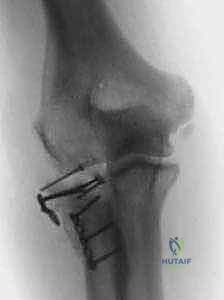

1. التثبيت الداخلي والرد المفتوح (ORIF - Open Reduction and Internal Fixation):

يتم إرجاع قطع العظم المكسورة إلى مكانها التشريحي الدقيق وتثبيتها باستخدام مسامير دقيقة جداً (Micro-screws) وشرائح معدنية صغيرة مصممة خصيصاً لرأس الكعبرة. تتطلب هذه العملية مهارة فائقة لضمان عدم إعاقة المسامير لحركة المفصل.

2. استبدال رأس الكعبرة بمفصل صناعي (Radial Head Arthroplasty):

في الكسور المفتتة بشدة (النوع الثالث والرابع) حيث يستحيل تجميع العظم، يقوم الدكتور هطيف باستئصال العظم المهشم واستبداله برأس كعبرة صناعي معدني متطور. هذه التقنية تضمن استقرار المرفق فوراً وتسمح للمريض بتحريك ذراعه في اليوم التالي للعملية.